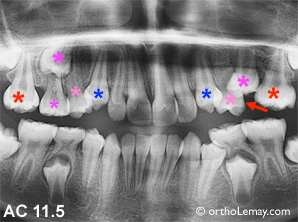

Cas AC : Ce patient plus vieux (11.5 ans) a le même problème du côté opposé; la première molaire supérieure gauche a fait tomber la deuxième molaire temporaire supérieure gauche beaucoup plus tôt que normal car elle sortait dessous la dent temporaire. Il y a une bonne partie de l’espace qui est perdue par la migration de la molaire (flèche) mais, pour éviter d’en perdre davantage, un mainteneur d’espace serait indiqué. La situation du côté gauche est plus normale mais le mainteneur protégera aussi ce côté lorsque la dernière dent temporaire sera perdue.